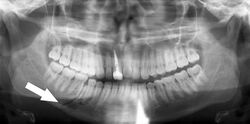

Panoramic radiograph showing horizontally impacted lower wisdom teeth.

Minimally-displaced fracture in right mandibular. Arrow marks fracture, root canal on central incisor, teeth to the left of fracture do not touch

Panoramic radiograph showing Stafne defect (arrowed).

Dental panoramic radiograph showing dentigerous cyst (arrowed).